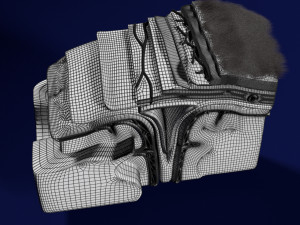

Brain with meninges scalp detailed labelled 3D 3D मॉडल

A blend model of brain along with its covering layers (meninges), skull bone and scalp labelled in detail and anatomically precise. The parts depicted are white, gray, pia, arachnoid, dura, bone, skin, fat, aponeurosis, periosteum, falx cerebri and more.

The material is high resolution image textures and normal maps based on non overlapping UVs. The texture and normal maps are packed with the blend file itself.